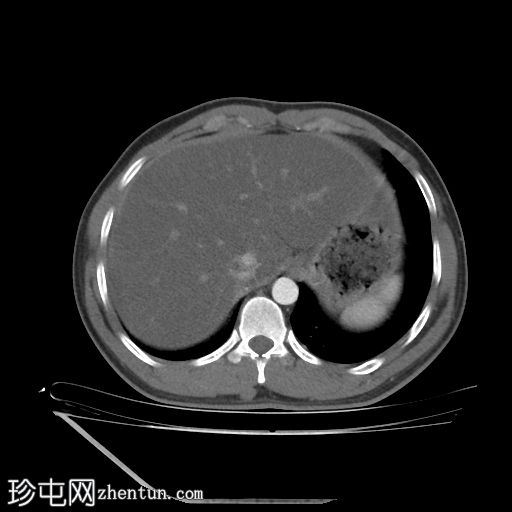

CT肾血管造影显示一条起源于左肾下段的副肾静脉,该静脉环绕主动脉走行,并接受来自腰静脉的属支,走行于主动脉后方,最终汇入下腔静脉。

双侧肾脏集合系统重复,分为上极和下极两部分。右侧输尿管在中段汇合,而左侧输尿管在进入膀胱前仍部分分离,符合双侧部分输尿管重复畸形(双分输尿管)。

左肾下极可见一大小约7毫米的皮质性囊肿。

本病例展示了一条环绕主动脉的副左肾静脉,其走行于主动脉后方并汇入下腔静脉,而右肾静脉解剖结构正常。

双侧肾动脉解剖结构正常,双侧肾动脉均起源于L2椎体水平的腹主动脉,管径正常,无狭窄、动脉瘤、夹层或副动脉。

双侧重复肾盂输尿管系统,上下极部分明显。右侧重复的输尿管在中段汇合,而左侧输尿管在进入膀胱前仍部分分离,符合双侧部分输尿管重复畸形(双分输尿管)。双肾大小、位置、轮廓和实质厚度均正常,造影剂浓度和排泄功能正常。未见肾结石、肾积水或局灶性肾脏病变。

左肾下极可见约7 mm的Bosniak I型单纯性皮质肾囊肿。